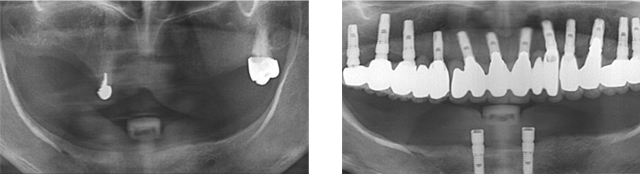

치아상실 상태가 오래 되어 적절한 영양섭취가 힘들어 “영양부족”으로 내원한 환자분. 우선 영양섭취를 위하여 음식물을 씹을 수 있는 임시치아를 빠르게 만들어 드렸습니다. 건강상태가 회복되어 상악은 12개의 임플란트를 식립 하고, 하악의 경우 잇몸 뼈가 많이 소실되어 2개의 임플란트를 식립하고 임플란트 틀니를 장착하였습니다.